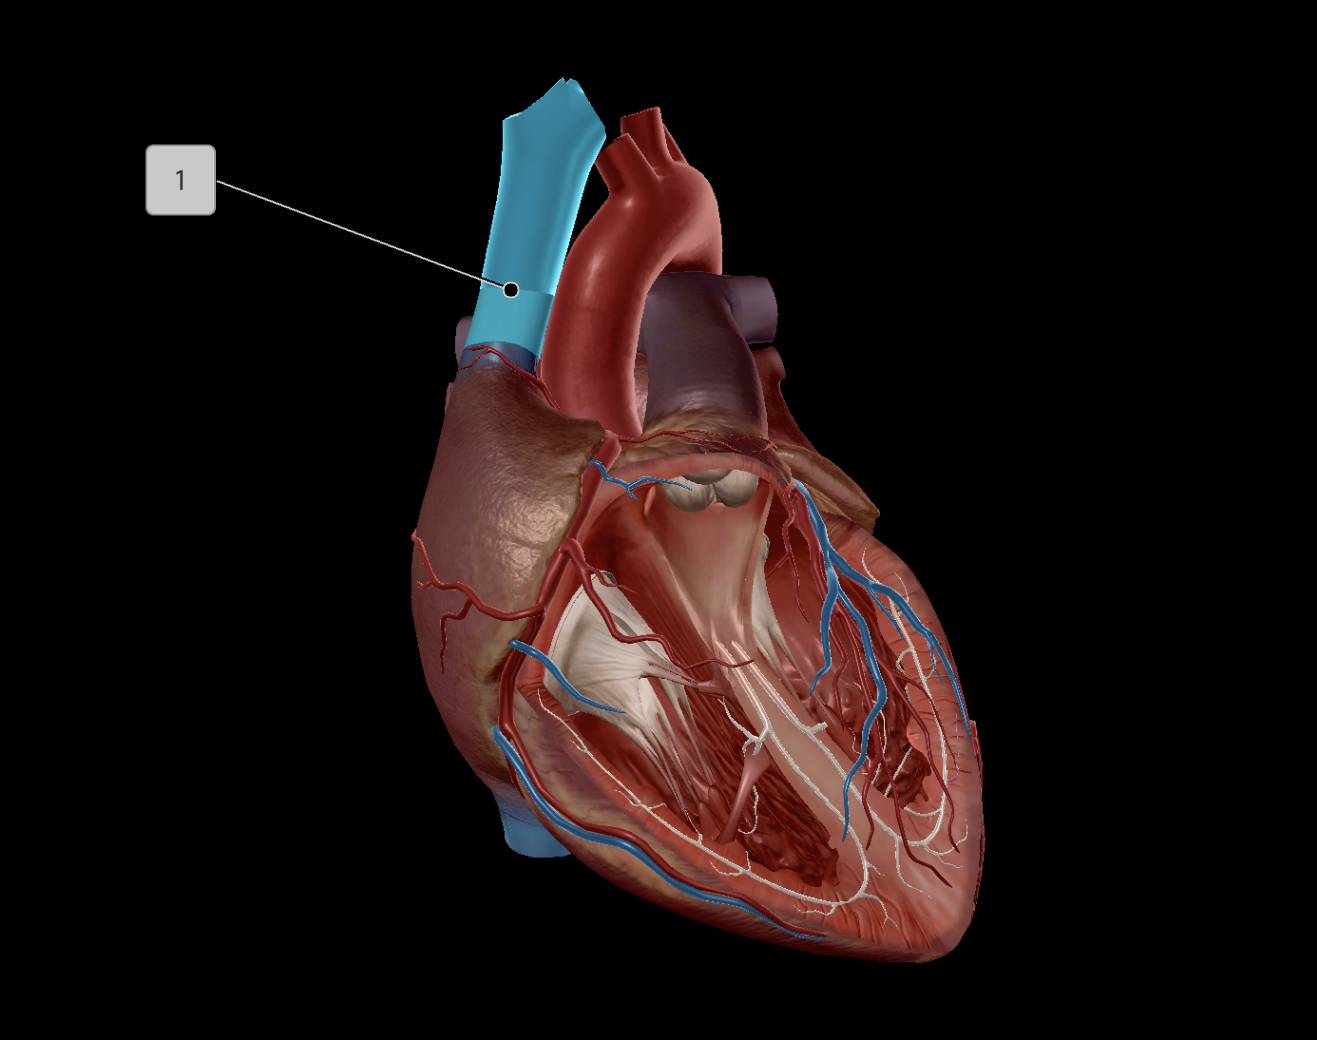

Superior Vena Cava

Pulmonary Trunk

Brachiocephalic Vein

Subclavian Vein

Pulmonary Artery

Left Atrium

Right Atrium

Left Ventricle

Right Ventricle